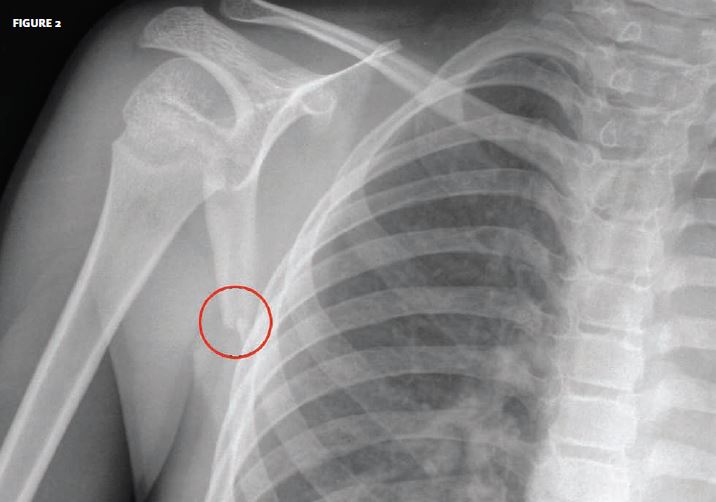

Scapula fractures in complex shoulder injuries and floating shoulders

Scapula fractures in complex shoulder injuries and floating shoulders Scapula Fracture Cycling Other orthopedic lesions of the shoulder include. Firstly, a typical riding position would place 40% of a rider’s weight on his upper limbs. The most common bony injury is a clavicle fracture, which represents around 45% of all recorded fractures due to bicycle accidents. What is a scapula injury and why have i got it? This is fairly considerable and. Scapula Fracture Cycling.